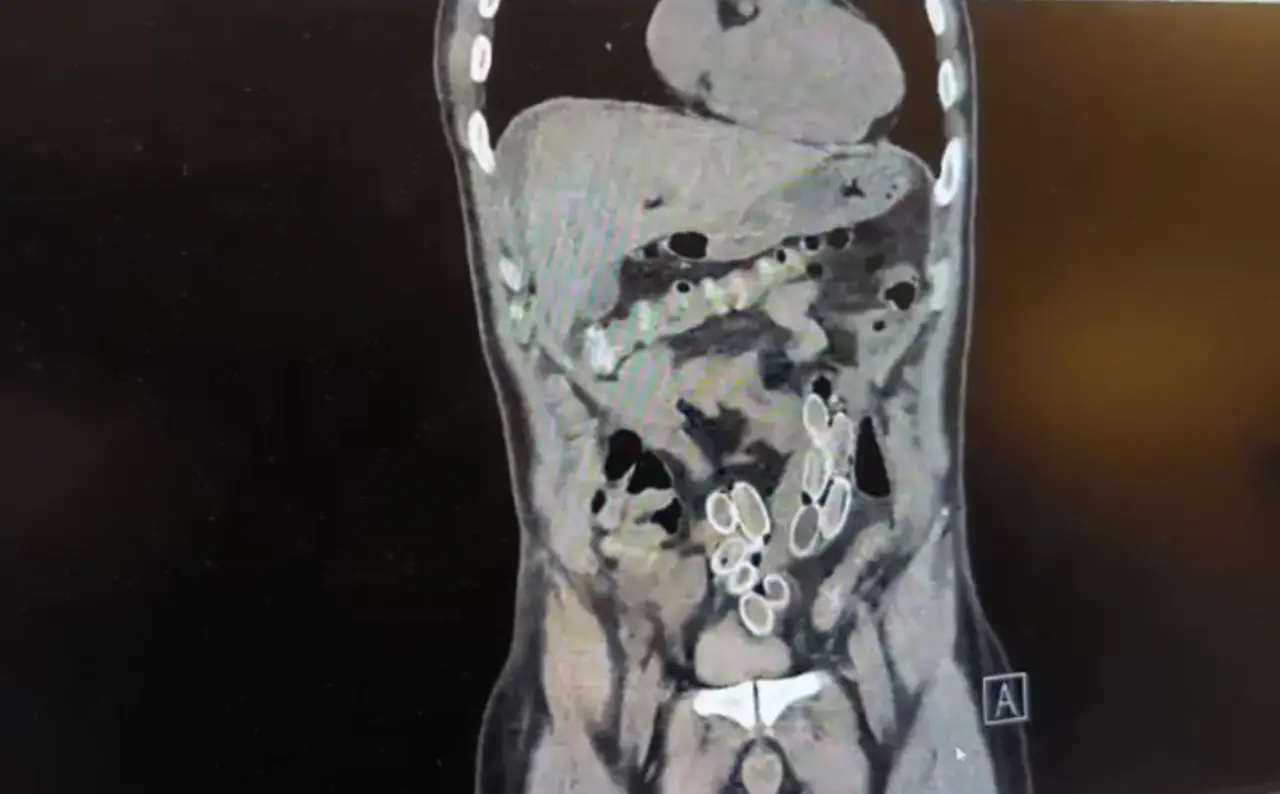

Fas’tan yaklaşık 3 bin kilometre uzaklıktan uçakla Türkiye’ye gelen Cüneyt G., 2 gün sonra karın ağrısı şikayetiyle Fulya’daki özel bir hastaneye başvurdu. Yapılan muayenenin ardından Cüneyt G.’nin tomografisi çekildi. Şüphelinin mide ve bağırsaklarında yabancı madde tespit edilmesi üzerine hastane yetkilileri durumu polis ekiplerine bildirdi.

İhbar üzerine çalışma başlatan Beşiktaş Asayiş Büro Amirliği ekipleri, doktorlarla görüşme gerçekleştirdi. Doktorların değerlendirmesi sonrası ameliyata alınan Cüneyt Ç.’nin bağırsaklarından, toplam ağırlığı 259,7 gram olduğu öğrenilen 49 esrar macunu çıkarıldı. Şüpheliye ait 1 adet cep telefonu da hastane yetkilileri tarafından polis ekiplerine teslim edildi.